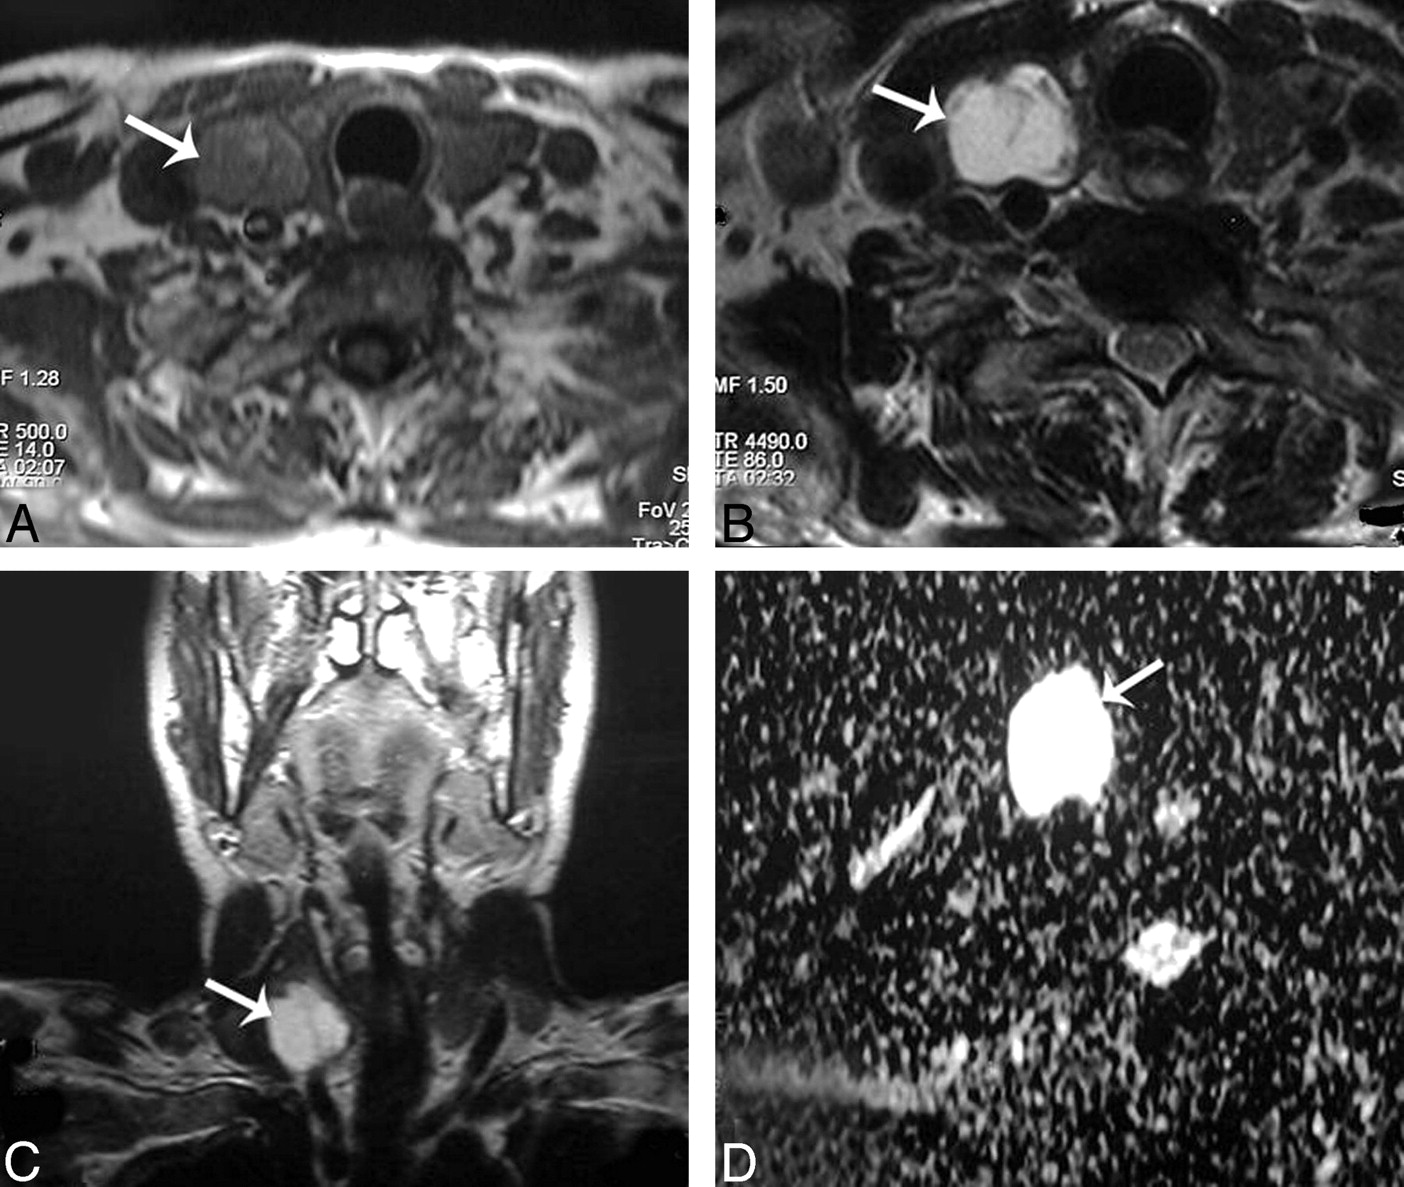

Table 1 illustrates the ADC values of the different histopathologic types of solitary thyroid nodules in this study. The ADC value of the adenomatous nodules ranged from 1.1 to 1.9 × 10−3 mm2/s (Fig 2). Also, the range of the ADC value of the solid part of the follicular adenoma was 1.2–2 × 10−3 mm2/s (Fig 3). The thyroid cysts (Fig 4) revealed the highest mean ADC value (1.9 ± 0.38 × 10−3 mm2/s) apart from 1 patient with hemorrhagic cyst (Fig 5), whose ADC value was 0.5 × 10−3 mm2/s, simulating malignant lesions. The malignant thyroid nodules showed lower ADC values (Figs 6 and 7). The mean ADC value of papillary carcinoma was 0.68 ± 0.23 × 10−3 mm2/s, and that of follicular carcinoma was 0.77 ± 0.17 ×10−3 mm2/s.

Adenomatous nodule. A–C, Axial T1- and T2-weighted and coronal T1-weighted MR images of the neck, respectively, showing a well-defined oval mainly solid solitary nodule (arrow) affecting the right thyroid lobe with contralateral tracheal displacement. D, An ADC map image with hyperintensity of the nodule (arrow) denoting increased diffusion and a measured ADC value of 1.57 ± 0.11 × 10−3 mm2/s.